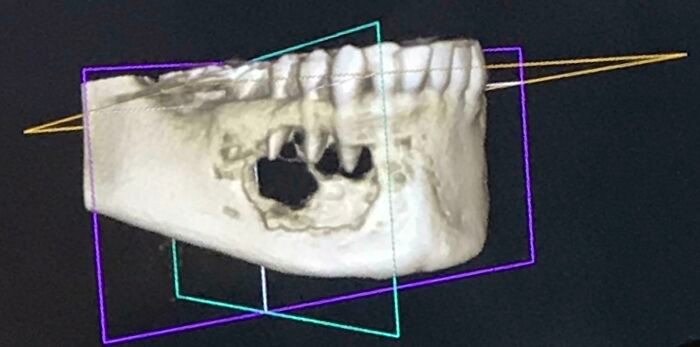

Kondisi Tubuh Manusia Ini Bikin Takjub dan Merinding